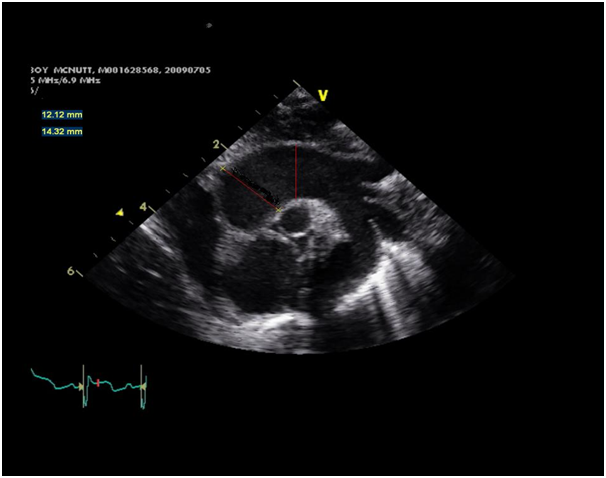

Baby boy A was born at 38weeks gestational age to a 20year old gravid mom. Pregnancy was uneventful. Mom was HIV negative, VDRL negative, HBsAg negative, Rubella immune and group B streptococcus positive. There was spontaneous onset of labour with rupture of membranes. He was delivered vaginally with Apgar scores of 4, 4 and 6 at 1, 5 and 10minutes respectively. He had no respiratory effort and was intubated. Birth weight was 3.16kg (50th percentile) and head circumference was 35cm (75th percentile). His size was appropriate for gestational age. Physical examination revealed jaundice, generalized petechiae and large hepatosplenomegaly. He was immediately started on intravenous antibiotics following a full septic workup. Laboratory investigations revealed a platelet count of 46,000, Urine culture was positive for Cytomegalovirus. Chest X-Ray/Abdomen X-Ray revealed small right sided pleural effusion, hepatomegaly 7.8cm and splenomegaly 8.8 cm. Ultrasound of the head revealed calcification in the basal ganglia bilaterally and a 9*9*7 mm cyst in the left temporal lobe adjacent to the temporal horn of the left lateral ventricle. Ophthalmology exam revealed bilateral retinal hemorrhages, but no chorioretinitis. Placental pathology showed features of chronic villitis with presence of plasma cells. Immunostaining in placental tissue was positive for CMV in 4 cells, but negative for Ebsteinbarr virus/ parvovirus/herpes virus 1 and 2 and toxoplasma. With findings suggestive of Congenital CMV infection, baby boy A was started on intravenous Gancyclovir. He was extubated on day 3 of life to low flow oxygen initially and then to room air. Antibiotics were discontinued after 48hrs of negative blood cultures. He was noted to have a murmur on physical exam. Echocardiogram revealed dilated ascending aorta with normal measurements of aortic valve annulus, aortic sinus and sinotubular junction. The supravalvular aorta was dilated (Z score 3.64, absolute measurement of 1.2cm), with maximum dilation seen at the level of the ascending aorta (Z score 6). It was a normal aortic valve, baby had good biventricular function with no LV dilation. There was no flow acceleration across the trileaflet aortic valve. The baby had normal hemoglobin and was not tachycardiac or febrile at the time of the Echocardiogram (Figure 1). A follow up echocardiogram done at 6 months of age revealed partial resolution of the dilation of the supravalvular aorta 1.37cm (Z score 2.72), ascending aorta 1.16cm (Z score 2.29).

Figure 1 Echocardiogram.